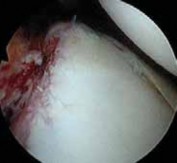

The surgical approach begins with the establishment of a standard posterior viewing portal, placed approximately 2 cm inferior and 1 cm medial to the posterolateral corner of the acromion. Upon entering the joint, a meticulous diagnostic sweep is performed. The surgeon must systematically evaluate the biceps anchor, the superior labrum, the articular surfaces of the humerus and glenoid, the rotator cuff footprint, and the entire capsulolabral complex. Particular attention is directed to the anteroinferior quadrant to confirm the presence of a Bankart or ALPSA lesion. The size and depth of any Hill-Sachs lesion are evaluated dynamically by taking the arm through a range of motion to assess for "engagement" over the anterior glenoid track.